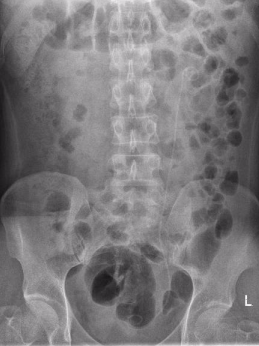

吴先生是一名办公室职员,近期总被间断性腰痛困扰,起初他以为是腰椎间盘突出,并未在意,直到腰痛加剧才到荆州市第一人民医院就诊。CT检查结果让他心头一紧——左侧肾脏竟藏着一颗直径2公分的结石,且已引发肾脏积液。

手术在医院日间手术病房顺利开展,吴先生术后无需留置肾脏引流管,身体状态恢复迅速,不到24小时就达到出院标准。出院时,他看着清晰的术后影像,连连感慨医疗技术的神奇与高效。

术前

术后